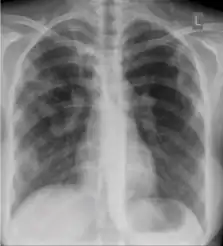

Chest x-ray showing coarse reticulonodular densities on the lower right lung of post-primary pulmonary TB. -